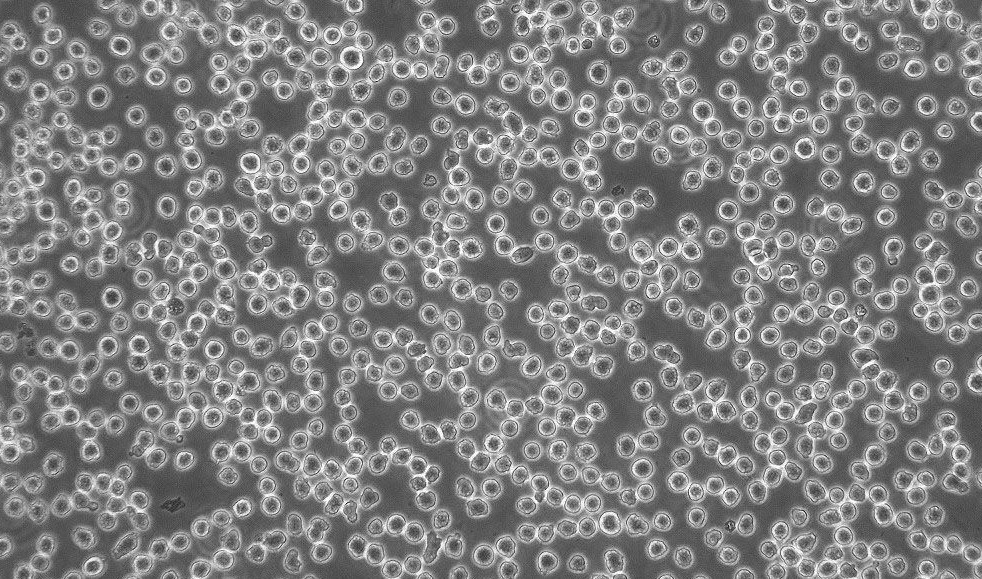

M 1; M-1 myeloid leukemia

M1